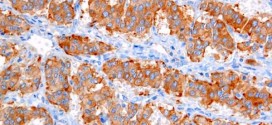

El fibrosarcoma. Tumor maligno constituido por células fusiformes (en forma de hueso) sin otra diferenciación celular, con colágeno y fibras de reticulina (sustancia albuminoidea de las fibras conjuntivas del tejido reticular) abundantes. Produce metástasis principalmente por vía hematógena. El Fibrosarcoma es un tipo de tumor maligno que se desarrolla a menudo en los extremos de los huesos de la pierna y …